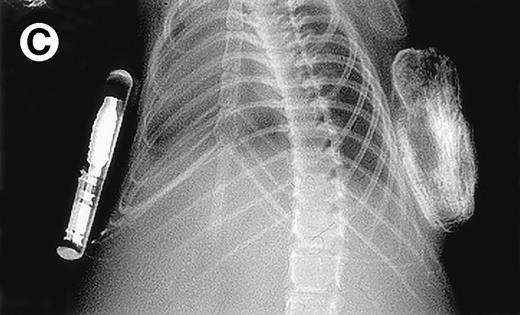

Growth of purified myeloma plasma cells (PC) from patient no. 1 in a SCID-hu host. SCID-hu host was inoculated with sorted PC. (A) Human Ig concentrations. (B) Dot plot of CD38/CD45 flow cytometry profile of the cells. The sort window used to purify plasma cells is shown. (C and D) X-radiograms showing severe resorption of the myelomatous implanted bone (C) compared with the nonmyelomatous bone of the control host (D), implanted at the same time as (C).